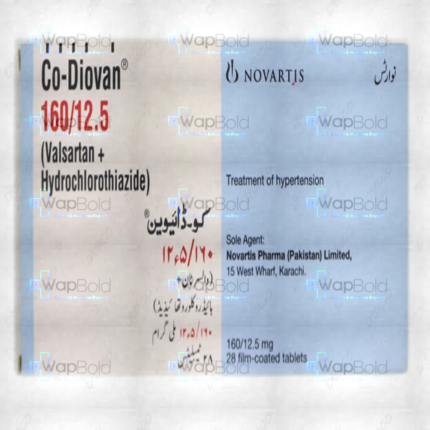

Co-Valstar Tablets 160Mg/25Mg (1 Strip = 7 Tablets)

₹646.80 Original price was: ₹646.80.₹614.50Current price is: ₹614.50.

- Variations: Strip

- Discount Amount On Strip: £32.3

- Prescription Required: Yes

- Strip: £646.0

- Used For: Hypertension

- Brand: C.C.L (Pvt) Ltd .

- Min Order Quantity: 20 units

- Min Order Price: ₹12936.00

Co-Valstar Tablets 160Mg/25Mg – 7 Tablets per Strip

Discover the power of Co-Valstar Tablets, designed to provide effective relief with each dose. Each strip contains 7 tablets, ensuring you have the right amount of medication at your fingertips. With a combination of 160mg and 25mg, these tablets are tailored to meet your needs. Whether you’re managing symptoms or seeking relief, Co-Valstar Tablets are here to help you feel better.

Key Features:

- Convenient Packaging: 7 tablets per strip for easy dosing.

- Effective Relief: Formulated with 160mg and 25mg for optimal results.

- Trusted Quality: Reliable and consistent medication for your well-being.

Experience the difference with Co-Valstar Tablets. Order now and take the first step towards better health.